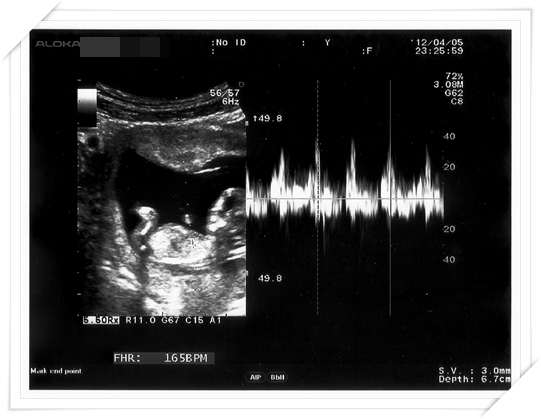

這次產檢 醫生也順便幫我做了頸部透明帶的測量

通常是跟第一期母血唐氏症篩檢一起做的

就是看看唐氏症的機率囉

然後做頸部透明帶的時候

醫生還順便照了照Baby 的鼻骨

給我們看看 baby 已經發育出來挺挺的鼻骨 (還好不像我扁鼻子!!!!)

但其實醫生是說 唐氏症寶寶比較容易沒有鼻骨 (鼻子扁扁的)

所以如果鼻骨有正常發育 是唐氏症寶寶的機率就會比較低囉

給我們另一個參考的小指標